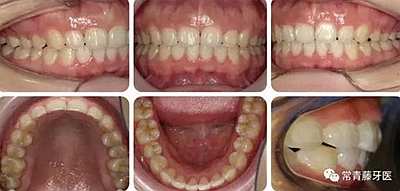

治療23個月結(jié)束??梢妰蓚?cè)尖磨牙達到中性關(guān)系,上下牙列排齊整平,前牙覆合覆蓋正常,中線齊。

結(jié)束3個月后復(fù)查,無明顯復(fù)發(fā)。

曲斷可見牙根基本平行。